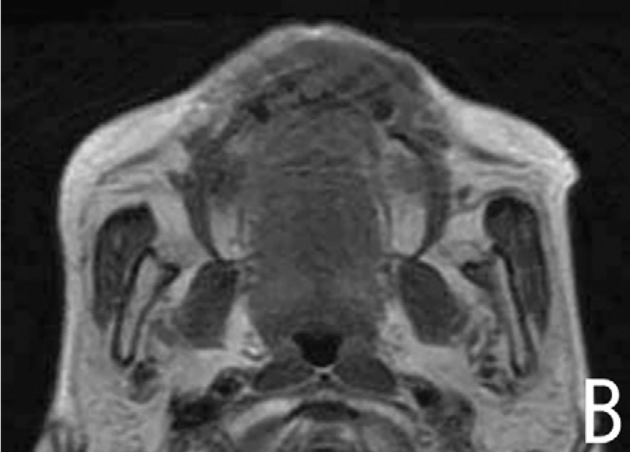

当常规治疗手段宣告效果不佳,肿瘤仍在体内肆虐时,患者心中的绝望难以言表。放疗、化疗带来的副作用还未褪去,身体的疼痛却日夜加剧,吃饭、睡眠这些最基本的生活需求都成了奢望。近日,东莞的一家医院成功应用国产首台直线型射频四极场硼中子俘获治疗(RFQ-BNCT)系统完成了一例复发鼻咽癌患者的全流程治疗。这个消息就像是一颗重磅炸...